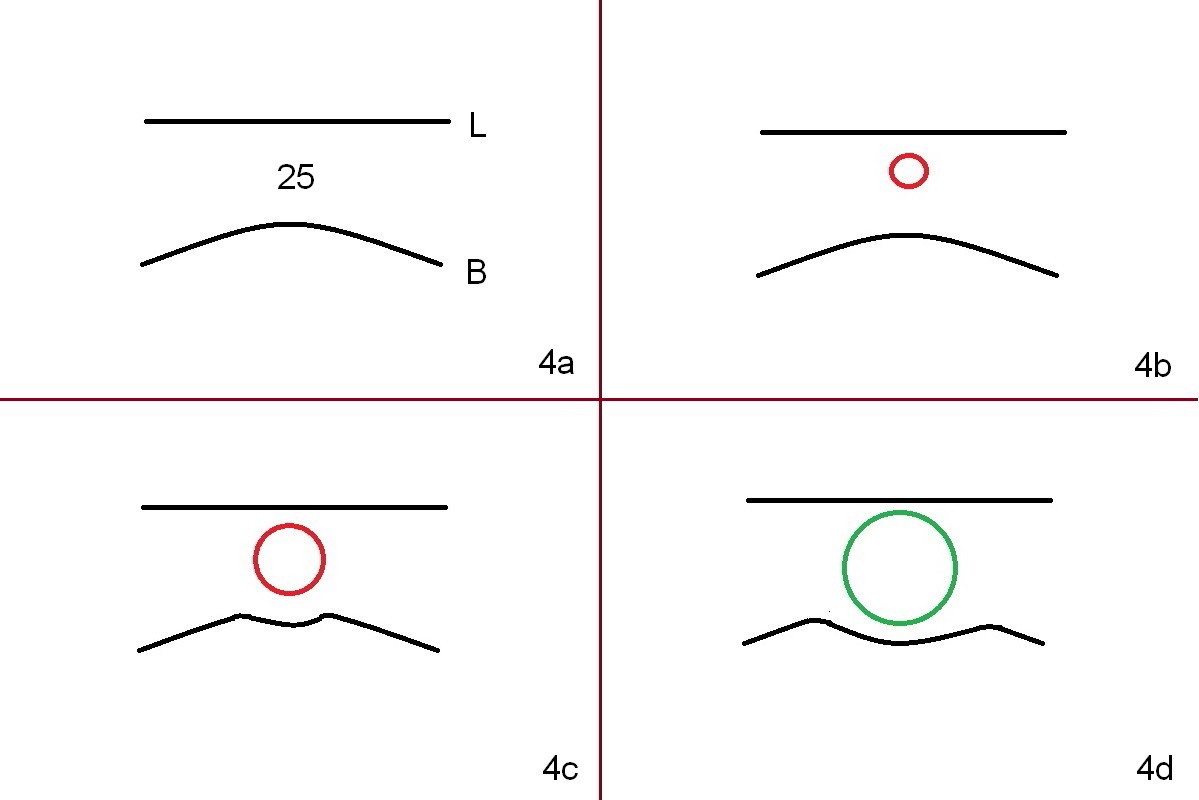

A 53-year-old woman (WX) had several missing teeth with a lower flipper (Fig.1,2, conditions 2 years ago). Recently the tooth #24 fractured equigingival (Fig.2 saw-toothed line). The edentulous area at #25 is narrow buccolingually (Fig.4a). Start osteotomy lingually (L, Fig.4b red circle). As the osteotomy increases (Fig.4c red circle) and a 2 or 2.5 mm 1-piece DIO implant is placed (Fig.4d green circle), the weaker buccal (B) plate is being expanded buccally.

A 3 or 3.5 mm 1-piece implant is placed at #24 (Fig.3) after Metronidazole socket soaking. The larger one is chosen (3.5 mm (Tatum)) if the implant at #25 fails to be placed. A dummy implant is placed partially to test trajectory. If the latter is bad, use an angled 1-piece one (Tatum). The composite overhang (Fig.2 *) is to be trimmed (Fig.3 red line). Take preop photos to show the concave buccal plate (Fig.4a) and intra- and post-op ones to show bone expansion (Fig.4b-d).